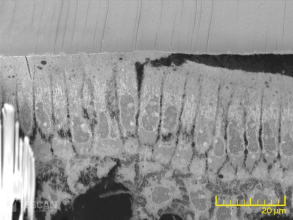

Trong Sinh học cấu trúc, việc phân tích cấu trúc tế bào cung cấp nhiều thông tin ẩn dưới bề mặt của tế bào và mô. Thiết bị điển hình sử dụng trong lĩnh vực nghiên cứu này là Kính hiển vi điện tử truyền qua (TEM). Tuy nhiên, công nghệ của Kính hiển vi điện tử quét SEM TESCAN đang trở nên phổ biến trong lĩnh vực này nhờ vào những cải tiến liên tục cho ra nhiều kỹ thuật mới. TESCAN cung cấp nhiều giải pháp hiện đại giúp cho các nhà khoa học thực hiện nghiên cứu các tế bào sinh học.

Cách tiếp cận đầu tiên là tích hợp đầu dò STEM vào bên trong buồng SEM, do vậy có thể chuyển đổi SEM thành thiết bị TEM ở điện thế thấp.

Đầu dò STEM hoàn toàn phù hợp với lưới tiêu chuẩn thường được sử dụng trong TEM

Một cách tiếp cận khác là sử dụng phân đoạn nối tiếp bên trong thiết bị SEM theo sau bởi hình ảnh. Việc phân đoạn được thực hiện bằng cách cài đặt một dao siêu vi phẫu vào bên trong buồng hoặc sử dụng trực tiếp công nghệ hội tụ chùm ion.

Bằng việc phân chia nối tiếp các mẫu, sau đó là phân đoạn và tạo ảnh, các nhà nghiên cứu có thể dễ dàng hình dung dữ liệu liên quan dưới dạng 3D.